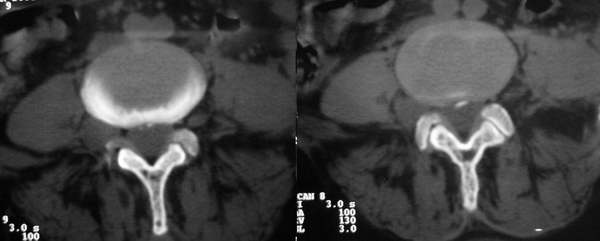

女:67岁,右下肢疼痛20余年。

行腰椎间盘扫描。

右侧椎间孔外侧见类圆形软组织肿块边缘清与右神经根关系密切

考虑神经鞘瘤

右侧椎间孔外侧见类圆形软组织肿块边缘清与右神经根关系密切。片子上标明了左和右了吗?正常的ct图像病变应该是在右侧呀!为和这么多人考虑或支持左侧!!!! 考虑右侧神经鞘瘤

此患者外院手术病理为:神经纤维瘤。在外院做mri平扫+增强,至今没照到mri图像感到遗憾。如果什么时间借到片子一定照下来传给大家。